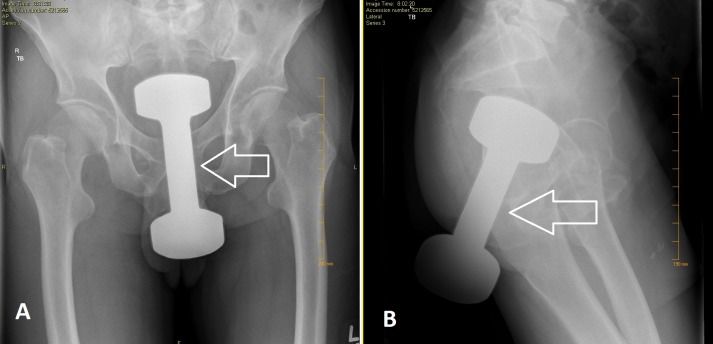

X-ray perlihatkan momen dumbbell masuk dubur Foto: Jurnal Cureus |

Kasus ini menimpa pria berusia 50 tahun di Pennsylvania, Amerika Serikat. Kasus tersebut tercatat dalam jurnal Cureus berjudul Successful Retrieval of a Retained Rectal Foreign Body in the Emergency Department.

"Benda asing di rektal adalah keluhan umum yang muncul di unit gawat darurat. Erosi anal adalah alasan utama sebagian besar kasus benda asing di dubur," tulis para peneliti.

Setelah dilakukan observasi, dokter menemukan dumbbell atau barbel seberat 2 kg tersangkut di tubuh pria itu. Pasien kemudian segera menjalani prosedur ekstraksi untuk mengeluarkan benda asing tersebut dari tubuhnya.

Untungnya, tak ada komplikasi yang terjadi setelah proses pengeluaran dumbbell dari duburnya. Pasca beberapa jam, pasien diperbolehkan pulang.